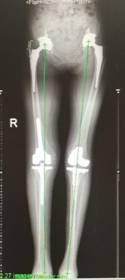

患者鄭女士,二十余年前患類風(fēng)濕性關(guān)節(jié)炎,幾乎沒有進行正規(guī)抗類風(fēng)濕治療,導(dǎo)致全身多處大小關(guān)節(jié)畸形、僵直、疼痛、無法行走、長期臥床、生活無法自理。來我院骨三科就醫(yī)時檢查發(fā)現(xiàn)除患者手足小關(guān)節(jié)嚴(yán)重變形外,雙髖雙膝四個關(guān)節(jié)也嚴(yán)重畸形喪失活動功能。左膝關(guān)節(jié)屈曲30°僵直、活動度為零;右膝關(guān)節(jié)外翻30°伸直位僵直、活動度為零;左髖關(guān)節(jié)僅有30°屈伸范圍;右髖關(guān)節(jié)伸直位僵直,活動度為零。如果要緩解關(guān)節(jié)疼痛,恢復(fù)部分關(guān)節(jié)功能需要進行雙髖關(guān)節(jié)和雙膝關(guān)節(jié)置換?;颊哂袊?yán)重骨質(zhì)疏松、關(guān)節(jié)畸形和長期類風(fēng)濕造成的器官功能損害,無論是從手術(shù)技術(shù)和圍手術(shù)期處理能力方面都是對醫(yī)療組的嚴(yán)峻考驗,陸斌副主任醫(yī)師團隊針對該患者的個體情況,經(jīng)匯報李蘇皖科主任和科室討論后,擬定了詳細(xì)和周密的手術(shù)方案,決定分期行雙髖雙膝關(guān)節(jié)置換,雖然增加了住院周期,但降低了圍手術(shù)期風(fēng)險,最大程度減少并發(fā)癥。整個治療約半年時間,目前患者可以扶拐行走,無關(guān)節(jié)疼痛,生活基本可以自理,患者非常滿意,近日出院。此例復(fù)雜疾病的獨立成功診治,表明我院骨三科(關(guān)節(jié)外科)技術(shù)水平在市內(nèi)領(lǐng)先的基礎(chǔ)上又更上一個臺階。